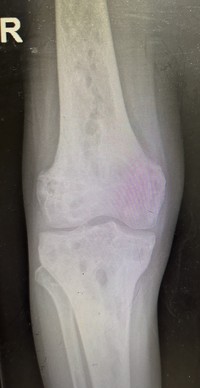

Lytic bone lesions with sclerosed margins 1

The patient also had complaints of multiple bone pains. X-Ray of lower limbs showed multiple lytic bone lesions with sclerosed margins.